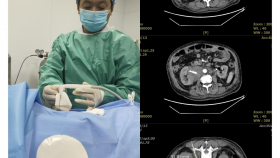

山东中医药大学第二附属医院肿瘤中心为省级中医药重点专科、重点学科,中华中医药学会血液病专委会创新研究与转化平台副主任及常委单位、山东中医药学会肿瘤精准医学专业委员会主委单位、山东中西医结合学会干细胞治疗专业委员会主委单位,是集医疗、教学、科研于一体的综合性科室。科室目前开放床位50余张,现有医疗、护理、技术人员30余人,其中山东省“泰山学者”岗位青年专家1人,主任医师2人,副主任医师2人,博士生导师1人,硕士及以上学历11人,形成了均衡发展的人才梯队。 科室拥有瑞典医科达直线加速器、德国西门子CT模拟定位机、瑞典Monaco治疗计划系统、美国Philips大型彩超、美国射频消融治疗机、康友微波消融治疗机、移动层流病床等一系列治疗仪器设备,主要收治多发性骨髓瘤、肺癌、结直肠癌、淋巴...